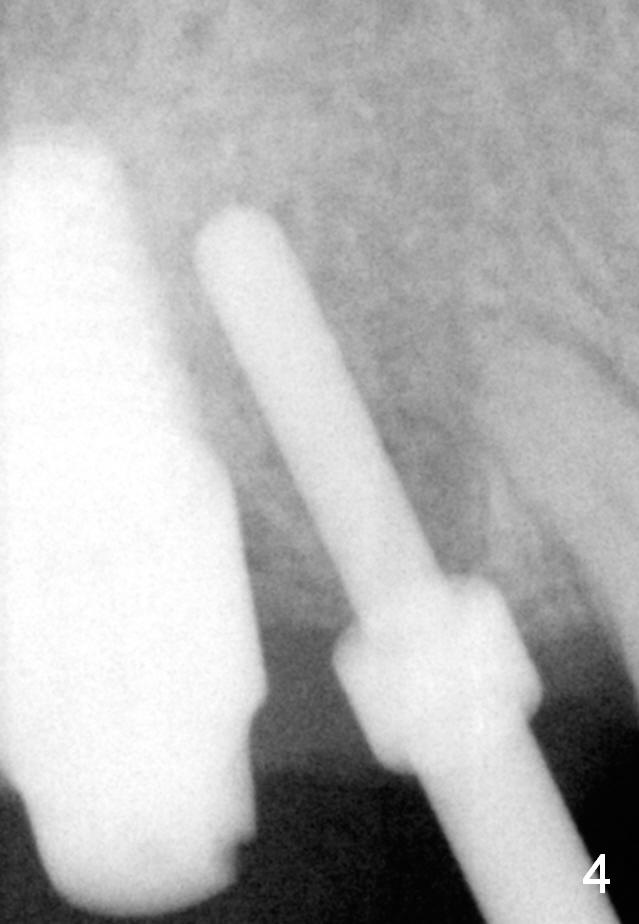

The implant at the site of #3 is intentionally placed distal as part of a plan to distalize the teeth #4-6 (Fig.1). Ortho started, but the patient did not want to pursue it. The most efficient way to terminate it is to dislodge every one of brackets/bands. When it is time for restoration for implants at the sites of #3 and 30, it is a challenge to deal with the space mesial to #3. The patient is planning to leave the country in 20 days. Fortunately he agrees to have an extra implant (Fig.2). It must be small in diameter. The initial osteotomy does not go on smoothly, approaching the apex of the tooth #4 (Fig.3 A). The osteotomy is moved distally and the trajectory is changed. It appears to be overcorrected (Fig.4). After re-adjustment, a 3.5x14 mm implant is placed with insertion torque between 15 and 20 Ncm (Fig.5). An abutment is placed with perio dressing applied around it as well as #3 after suturing. When the wound heals and before the patient leaves the country, the abutment is removed.

Eight months postop (Fig.6), he returns for final restorations (Fig.7 (buccal), 8 (lingual view)). There is no bone loss nearly 2 years post cementation (Fig.9).